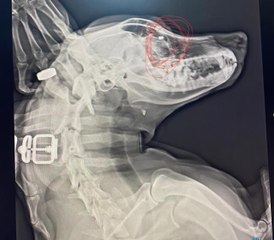

Sivas'ta 80 yaşındaki bir cani bahçesinde kafasına çuval geçirdiği eşeğini sopayla döve döve öldürdü.